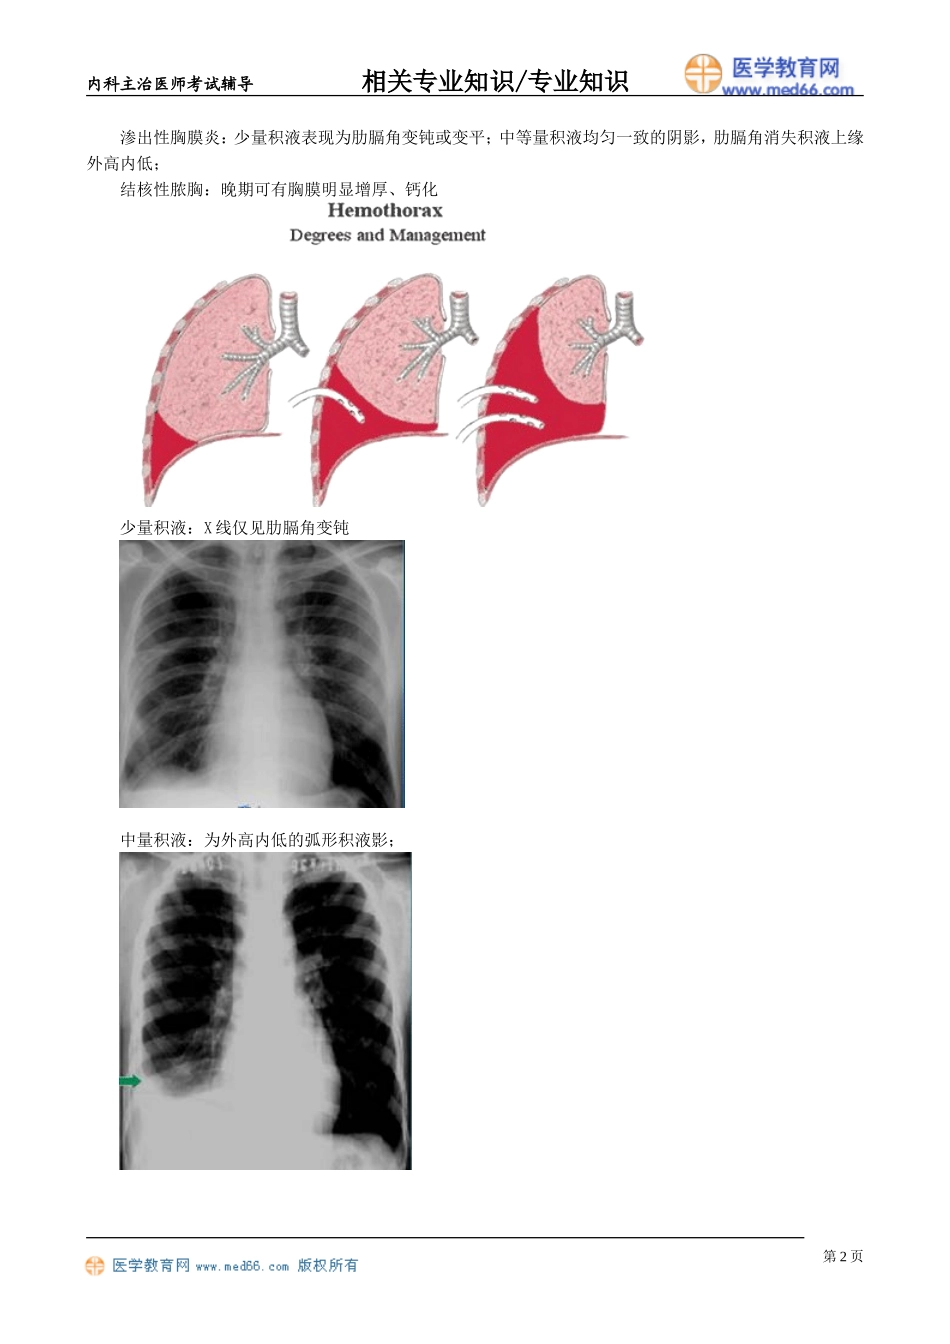

内科主治医师考试辅导相关专业知识/专业知识结核性胸膜炎发病机制1.结核杆菌及代谢产物到达胸膜。2.机体对结核杆菌及其代谢产物敏感性增高。结核性胸膜炎的结核杆菌主要来源:1.直接蔓延:肺部、脊柱、椎旁脓肿及胸壁结核等2.病灶破溃:干酪病灶、空洞破裂3.淋巴逆流到胸膜:淋巴结肿大影响淋巴结引流4.血行播散临床表现1.症状胸痛:干性胸膜炎,与呼吸、胸水有关。发热:多为不规则热、张弛热39~40℃呼吸困难:渗出性胸腔积液,量大、小皆有其他:结核病共性特点2.体征干性胸膜炎:胸膜摩擦音渗出性胸膜炎:视诊:患侧呼吸运动减弱叩诊:浊音或实音触诊:语音震颤减弱或消失脓胸:慢性病容,患侧胸廓塌陷,肋间隙变窄,气管纵隔患侧移位。影像学检查X线表现干性胸膜炎:多无X线征象第1页内科主治医师考试辅导相关专业知识/专业知识渗出性胸膜炎:少量积液表现为肋膈角变钝或变平;中等量积液均匀一致的阴影,肋膈角消失积液上缘外高内低;结核性脓胸:晚期可有胸膜明显增厚、钙化少量积液:X线仅见肋膈角变钝中量积液:为外高内低的弧形积液影;第2页内科主治医师考试辅导相关专业知识/专业知识大量积液:外高内低的弧形液影超过下肺野范围可视为大量,纵隔向健侧位移诊断1.干性胸膜炎有结核病史或结核接触史临床特点:发热、干咳、胸痛和胸膜摩擦音胸膜活检:典型的结核病理改变可确诊结核菌素试验多呈阳性反应抗结核治疗有效有助于诊断2.渗出性胸膜炎有结核病史或结核接触史临床表现:呼吸困难X线表现、超声波检查:胸腔积液征象结核菌素试验:多呈阳性反应抗结核治疗有效有助于诊断胸水检查的特点:渗出液多呈草黄色,少数为血性胸水。急性期多核细胞为主,以后以单核细胞为主。多数情况下胸水ADA>45IU/L。病源学检查:找结核菌和胸水结核菌培养的的阳性率不高。胸膜活检:典型的干酪样坏死病变或抗酸染色阳性可确诊。鉴别诊断见胸腔积液治疗见肺结核第3页